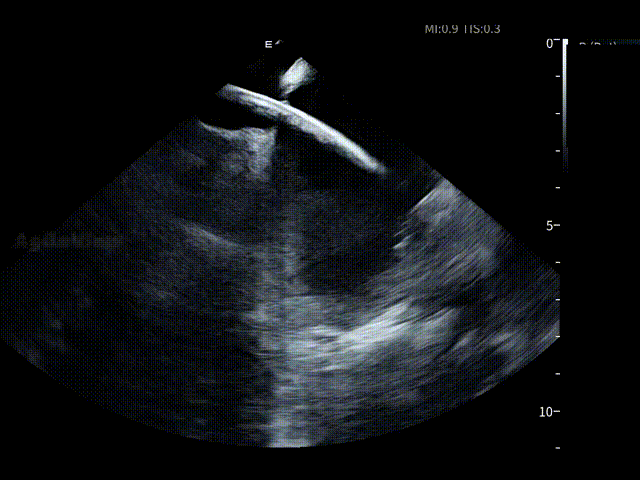

在全球最细7.5Fr ICE的持续影像引导下,手术路径清晰。随后,邹操教授在ICE下进行了房间隔穿刺,可见明显tenting现象。

房间隔穿刺